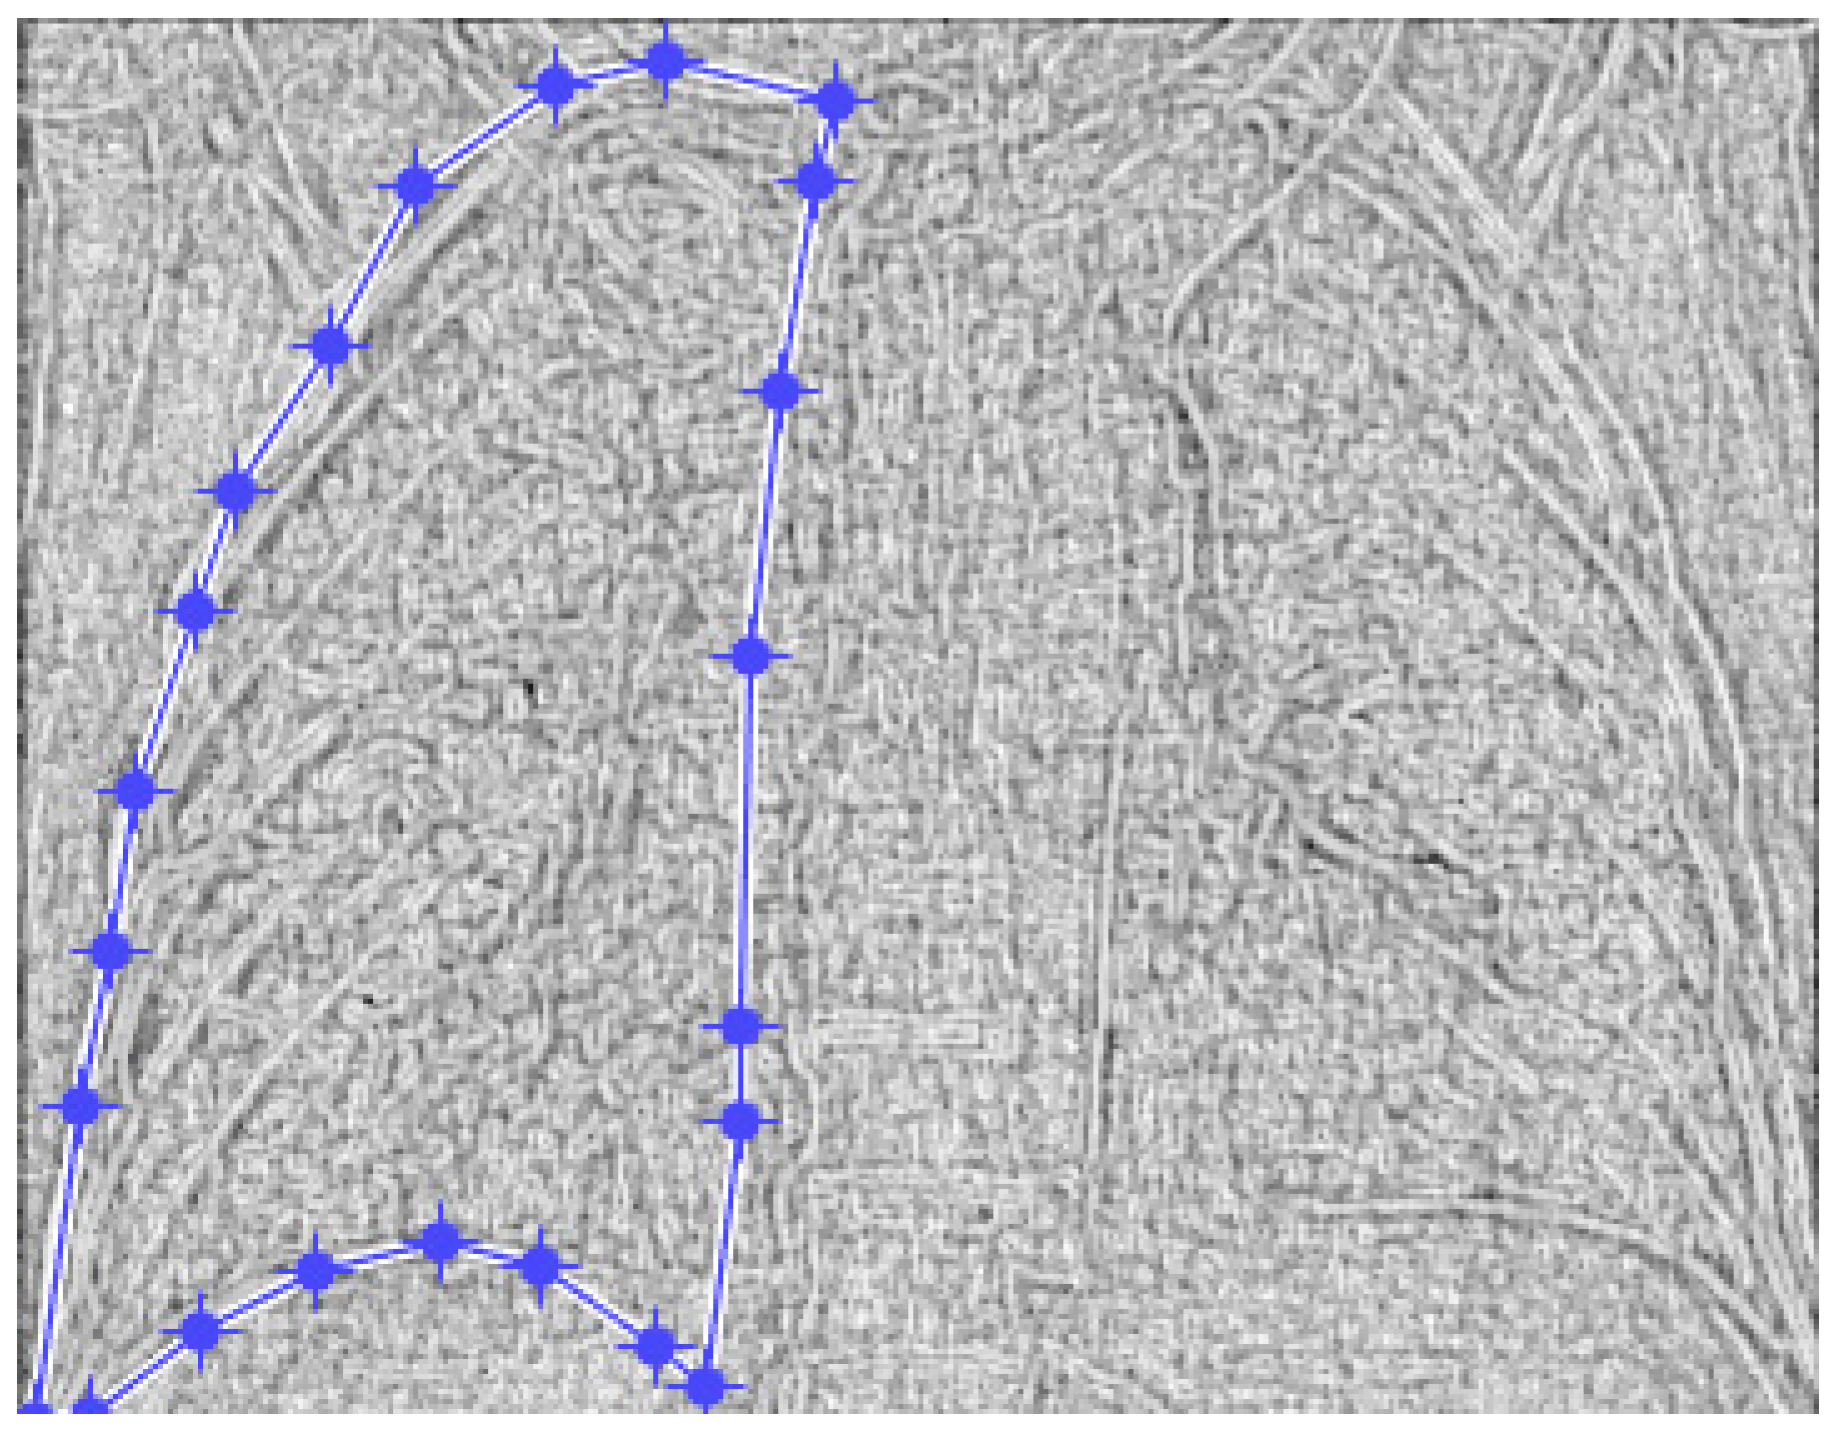

Figure 2 and Figure 3 show the selection of the lung portion of interest for patient MT and the same image in “Invert color” format.

Figure 4 and Figure 5 present the defined masks for the left lung and right lung, framed in blue borders.

Figure 2. The selection of the portion of interest of the lungs of patient MT.

Figure 4. Defining the mask for the left lung of the first patient.